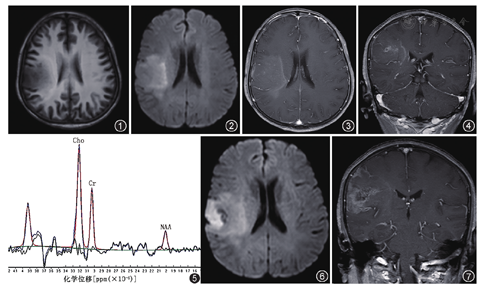

影像表现:头颅常规MRI(2016年6月30日)表现:右侧额顶叶见片状稍长T1、稍长T2信号,边界不清,内见散在小片状长T1、长T2信号,DWI(b=1 000 s/mm2)扩散受限呈不均质高信号,增强后强化程度较对侧正常区域稍增加,内部散在片絮状及环状明显强化的区域,病灶外围见多发线状强化,病灶周围未见明确水肿带,病灶区脑沟稍变窄,右侧脑室形态正常(图1,图2,图3,图4)。头颅功能MRI(2016年6月30日)表现:对患者进行单体素MRS扫描,选取生化代谢物指标:N-乙酰天冬氨酸(N-acetylaspartic acid,NAA)、胆碱(Choline,Cho)及肌酸(Creatine,Cr)。MRS分析结果:病灶内明显强化区域NAA/Cr 0.29,Cho/Cr 2.18,Cho/NAA 7.63(图5);正常对照区域NAA/Cr 2.56,Cho/Cr 0.96,Cho/NAA 0.37。同时还对该患者进行MR动态对比增强(dynamic contrast enhancement,DCE)扫描,采用Extended Tofts Linear模型进行后处理分析,选取反映微血管通透性的定量参数指标:容积转移常数(Ktrans)、回流速率常数(Kep)及血管外细胞外容积分数(Ve),选取T1灌注指标为脑血容量(cerebral blood volume,CBV)。DCE分析结果:病灶内明显强化区域Ktrans=1.100 min-1,Kep=1.080 min-1,Ve=0.770,CBV=82.752 ml/g;线状强化右侧肿瘤区域Ktrans=1.137 min-1,Kep=1.692 min-1,Ve=0.651,CBV=75.364 ml/g;线状强化左侧可能正常区域Ktrans=0.012 min-1,Kep=0.099 min-1,Ve=0.179,CBV=52.857 ml/g;对侧正常区域Ktrans=0.003 min-1,Kep=0.118 min-1,Ve=0.100,CBV=47.446 ml/g。复查头颅MRI(2016年8月17日)表现:DWI(b=1 000 s/mm2)扩散受限程度较前片(2016年6月30日)明显,范围较前片增大,增强后病灶内部明显强化的区域增大,由前片斑片状发展为片状,内部出现囊变坏死,病灶外围线状强化消失,局部软脑膜可见强化(图6,图7)。

本例间变性少突胶质细胞瘤的早期影像表现实属罕见,有以下几点不符合该类肿瘤常见的影像表现:(1)肿瘤边界不清,占位效应不明显;(2)病灶周围无水肿带;(3)肿瘤强化不典型,病灶呈轻度絮状强化为主,内部散在斑片状及环状强化明显的区域;(4)病灶外围线状强化,疑似肿瘤边界区域,后续随访消失。患者有直肠癌病史,但肿瘤不符合转移瘤小肿瘤大水肿的影像表现。MRS可见NAA峰(神经元标志物),病灶内明显强化的区域Cho峰(肿瘤标志物)升高,NAA峰降低,Cho/NAA比值大于6,提示为高级别神经上皮起源的肿瘤[6]。DCE示病灶区Ktrans平均值较对侧正常区域明显升高,符合高级别胶质瘤血脑屏障破化后改变[7,8],磁共振T1灌注结果进一步佐证了肿瘤区微血管的改变。针对患者(2016-06-30)T1WI增强病灶外围出现的线状强化,选取3个感兴趣区进行DCE分析,包括线状强化右侧肿瘤区域、线状强化左侧可疑正常区域及对侧正常区域,DCE分析结果可知线状强化左右侧血管通透性差异明显,考虑出现线状强化可能是肿瘤早期血脑屏障破坏后所致的反应性强化,后期随访消失,可能是机体适应及代偿后表现。